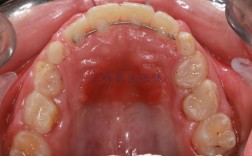

- 牙根形态与长度评估:通过根尖片或CBCT(锥形束CT)检查牙根形态,观察是否存在锥形牙根、弯曲牙根、牙根过短或牙根吸收史(如既往创伤、正畸史导致的吸收),CBCT可三维重建牙根结构,清晰显示牙根表面是否有凹陷、吸收陷窝等,比传统根尖片更敏感。

- 牙周状况检查:牙周健康是牙齿移动的基础,需评估牙龈指数、牙周袋深度、牙槽骨高度等,若存在牙周炎(牙槽骨吸收超过根长1/3),需先进行牙周治疗,控制炎症后再开始正畸,避免炎症状态下牙根移动加重吸收。